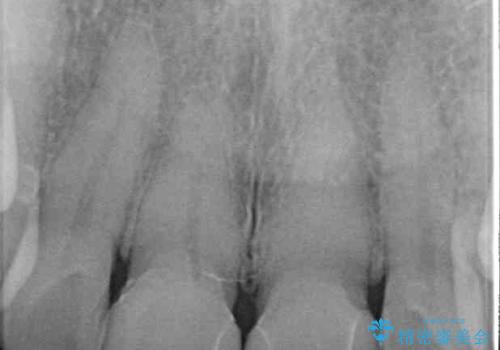

統一感のあるきれいな色調となり、患者様には大変満足していただきました。

仮歯に置き換えた後にオールセラミッククラウンにて補綴治療を行うこととしました。